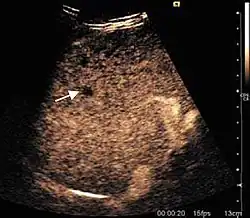

The ultrasound appearance is a well defined lesion, with very thin, almost unapparent walls, without circulatory signal at Doppler or CEUS investigation. The content is transonic suggesting fluid composition. The presence of membranes, abundant sediment or cysts inside is suggestive for parasitic, hydatid nature. Posterior from the lesion the acoustic enhancement phenomenon is seen, which strengthens the suspicion of fluid mass. They typically displace normal liver vessels but no vascular or biliary invasion occurs.

-

Liver cyst -

Hydatid liver cyst. Diagnostic criteria are the presence of membranes and sediment inside.